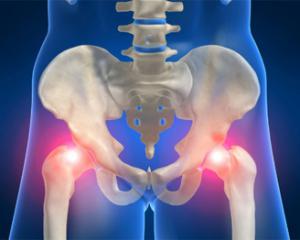

Артроз тазобедренного сустава — распространенное заболевание, вызывающее дискомфорт и ограничение подвижности, особенно у пожилых. В статье рассмотрим симптомы, причины и стадии артроза, а также методы лечения: медикаментозную терапию, физиотерапию и хирургические вмешательства. Понимание этого заболевания поможет читателям распознать его признаки и обратиться за медицинской помощью, что может улучшить качество жизни и предотвратить осложнения.

Артроз тазобедренного сустава — это распространенное заболевание, которое может вызывать значительный дискомфорт и ограничивать подвижность. Врачи выделяют основные симптомы, такие как боль в суставе, утренняя скованность и хруст при движении. Эти проявления могут существенно снизить качество жизни пациента.